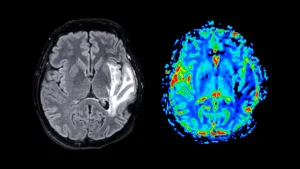

A significant breakthrough in Alzheimer’s disease research has emerged from Washington University School of Medicine in St....

Recent scientific investigations have illuminated a critical vulnerability in the cognitive architecture of Alzheimer’s disease, suggesting that...

A significant advancement in understanding the intricate molecular underpinnings of Alzheimer’s disease has been achieved by a...